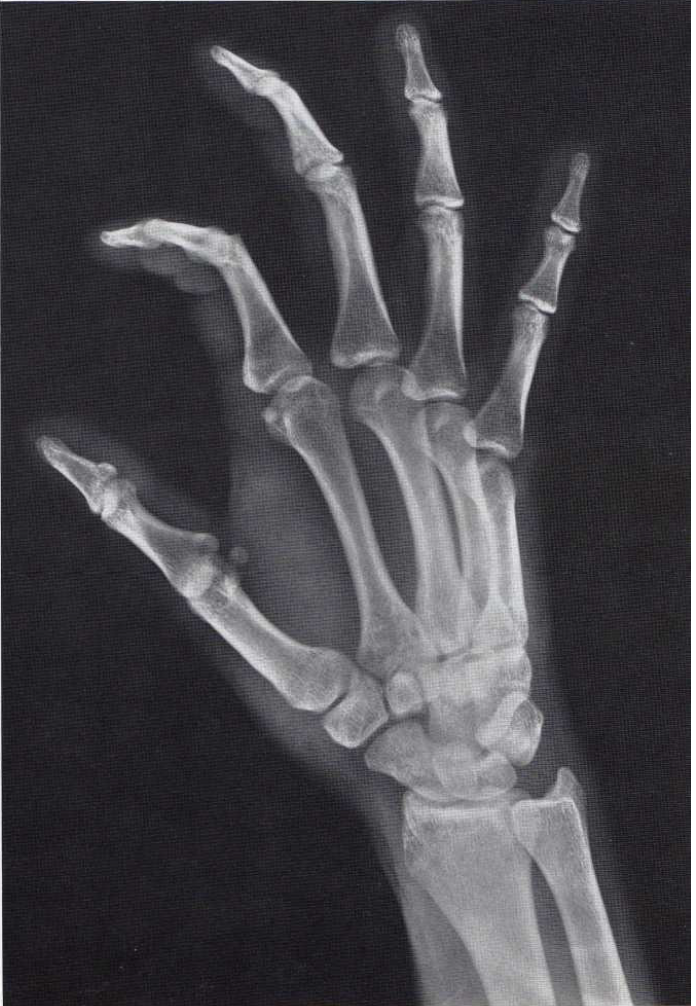

What is this view of the hand? What views are missing?

PA

MISSING:

Lateral

Lateral Oblique (PA)

Medial Oblique (PA)

Scaphoid